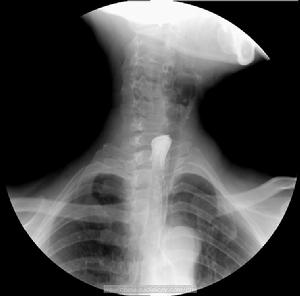

食管內異物1.影像學檢查影像學檢查是判斷有無食管異物及異物停留部位的一種有效的輔助檢查。

(1)X線檢查:X射線對不透光的異物如金屬異物具有決定性的診斷意義。但某些薄性骨片可因顯影差或體積較小而不能在透視上看出,則行X線正、側位拍片。值得注意的是文獻中曾有誤將甲狀軟骨及環狀軟骨的局限性骨化誤診為骨性異物的報導。

一些間接的放射影像學徵象有助於異物的診斷如椎前軟組織的腫脹增厚氣管和食管移位、Zenker憩室上縱隔增寬等。食管穿孔的最常見的初期放射學改變為食管周圍存有氣體。